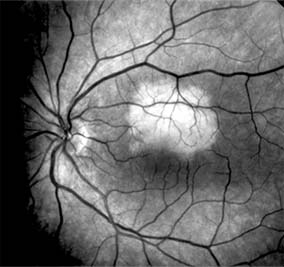

MYOPIC MACULAR DEGENERATION

Pathologic myopia is one of the leading causes of blindness in the United States and is characterized by progressive elongation of the eye with subsequent thinning and atrophy of the choroid and pigment epithelium in the macula. Peripapillary chorioretinal atrophy and linear breaks in Bruch's membrane ("lacquer cracks") are characteristic findings on ophthalmoscopy (Figure 10-10). The degenerative changes of the macular pigment epithelium resemble those found in the older patient with age-related macular degeneration. A characteristic lesion of this disease is a raised, circular, pigmented macular lesion called a Fuchs spot. Most patients are in the fifth decade when the degenerative macular changes cause a slowly progressive loss of vision; rapid loss of visual acuity is usually caused by serous and hemorrhagic macular degeneration overlying a subretinal neovascular membrane.

Figure 10-10

Figure 10-10: Myopic macular degeneration with choroidal vessels (arrows) visible through atrophic retinal pigment epithelium.

Fluorescein angiography in patients with pathologic myopia may show delayed filling of choroidal and retinal blood vessels. Angiography is helpful in identifying and locating the site of subretinal neovascularization in patients who develop serous or hemorrhagic detachments of the macula. Because of the frequent close proximity of the subretinal neovascular membrane to the foveola in these patients, laser photocoagulation may not be possible. As subretinal neovascular membranes tend to remain small and because photocoagulation-associated chorioretinal atrophy tends to progress in patients with pathologic myopia, retinal laser treatment is not as beneficial as in other diseases associated with macular subretinal neovascularization.